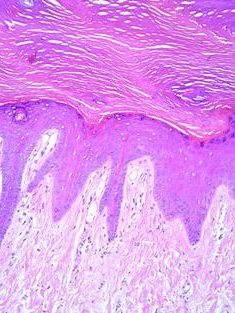

It’s worth mentioning that the border between the epidermis and the dermis is highly textured. They interlock in a zipper like formation which maximizes their surface area, allowing blood in the dermis to most efficiently supply nutrients to generative basal cells in the epidermis. This feature makes the exact depth of the epidermis difficult to calculate, but it increases our skin’s sensitivity as the nerves in the dermis can get closer to the surface.

Extensive trauma from the needles reveals that the epidermal-dermal junction is largely destroyed.

The dermal-epidermal junction has fully regenerated.

Dermal macrophages containing ink particles are spread throughout the upper portion of the dermis, and each cell is tightly surrounded by the rebuilt collagen network.